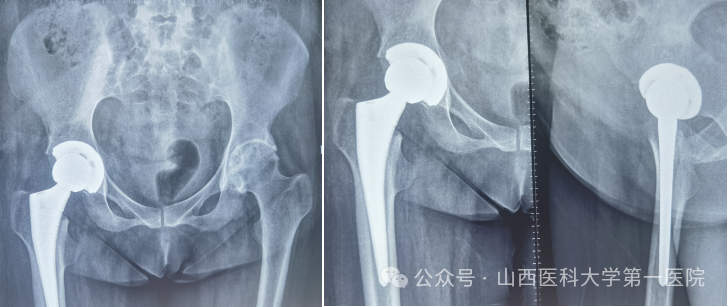

针对患者复杂病情,科室组织多学科讨论。为实现从“站坐难安”到“稳步前行”,杨自权主任团队决定先为患者实施“右侧人工全髋关节置换术”。术中,团队凭借精湛技术,精准处理强直融合的关节结构,在保护周围神经血管的同时,成功植入新的人工关节假体。

图片